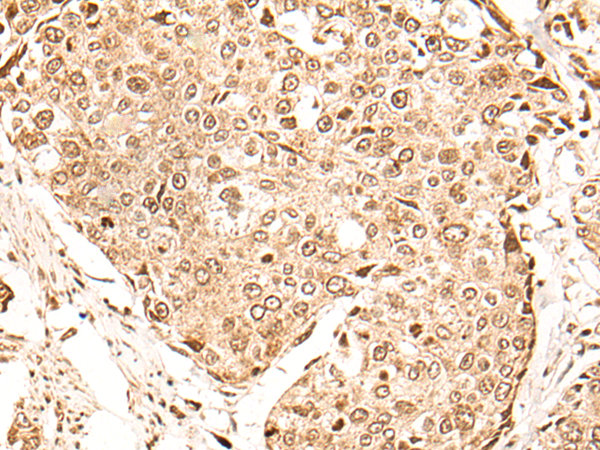

IHC positive control: |

Human thyroid cancer and human cervical cancer |